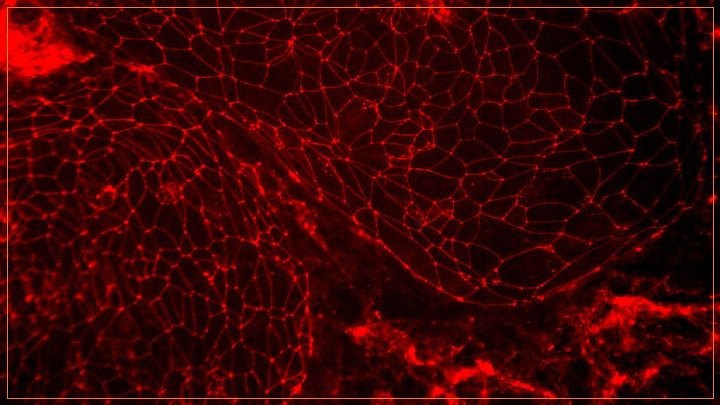

To get to treatments, new approaches to discovery are needed. Our team operates at the juncture of preclinical and clinical research to understand dysfunction of brain barriers (vasculature) in dementia-causing diseases. We measure molecular vascular contributions to cognitive impairment and dementia (VCID) in living humans. We use brain tissue, blood, CSF, all sorts of imaging, clinical phenotypes, and advanced data analytics to identify molecular drivers of disease and develop biomarkers for early detection and drug discovery.

Dysregulated angiogenesis in dementia project—a story of brain barriers and inflammation

In parallel to unbiased discovery projects, we are testing the relevance of druggable vascular targets, such as pathological angiogenesis, in brain degenerative diseases. Our models have shown that dysregulations in angiogenesis and blood-brain barrier dysfunction are correlated with slowed processing speed and executive dysfunction. We are improving these models these with the goal of identifying therapeutic opportunities. In addition, we are building in vitro experimental read-outs for these pathologies with the goal of identifying molecular interventions that could preserve brain health.